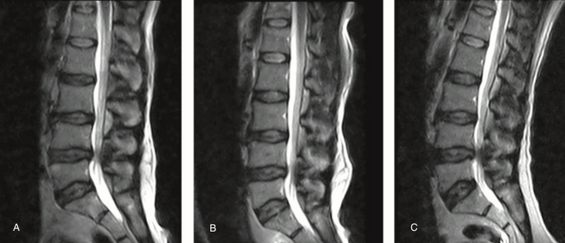

腰椎管狭窄的MRI检查!